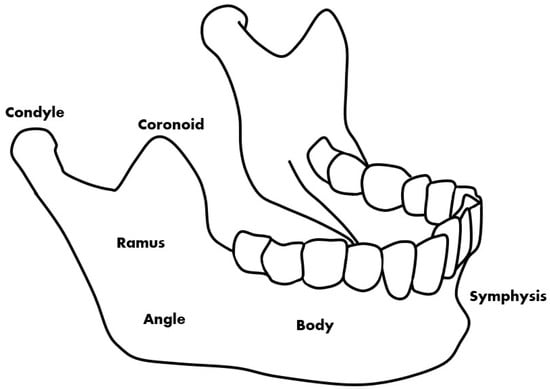

Mandibular fractures are a type of fracture treated in dentistry that are commonly caused by accidents []. Patient opinion, panoramic radiographic images, and CBCT (cone-beam computed tomography) images are used for the diagnosis of fractures. Panoramic radiography and CBCT are mainly used to confirm the exact size and location of the fracture during the diagnosis of the patient’s painful area []. Fracture locations that are difficult to identify in a panoramic radiographic image are identified through a CBCT image. Deep learning methods using CT are also being studied and it can be confirmed that they have high accuracy []. However, because CBCT takes a long time to perform and is more expensive than panoramic radiographs [,], this study introduces image deep learning technology to help determine the location of fractures from panoramic radiographic images. This helps the doctor to make a visual diagnosis and can assist in the identification while conserving time and cost. On panoramic radiographic images, the fracture site can be divided into six parts based on anatomical standards []. The fracture site is divided into the symphysis, body, angle, ramus, condyle, and coronoid, the most common of which are the symphysis, body, and angle (Figure 1) [].

Figure 1.

The types of mandibular fractures by region.